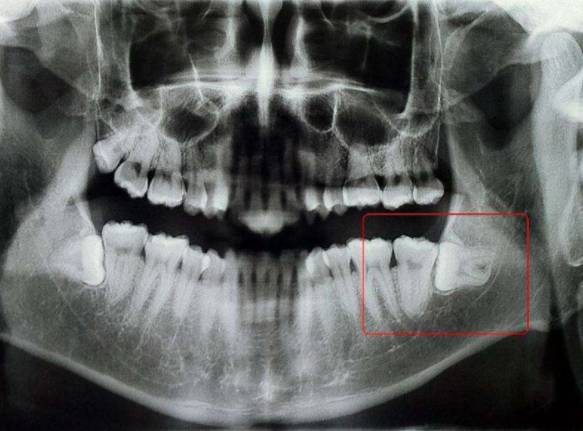

很多人都有疑问,我的智齿目前不疼不痒,我为什么要拔?智齿目前虽然没有引起问题,但是随着其生长,势必或者存在很大几率引起口腔问题,这就需要预防性拔除智齿。怎么知道自己的智齿要不要拔呢——拍片检查

1、拍片后确定智齿的位置方向,如果有足够的空间、方向正常,医生评估能顺利长出的话,可以考虑保留等待智齿自然长出。

2、如果拍片后牙齿位置不正,无法长出还对旁边邻牙造成威胁的,应当尽早拔除。若智齿没有及时拔除导致邻牙蛀牙的例子很多。80%的人的智齿位置长的都不正。